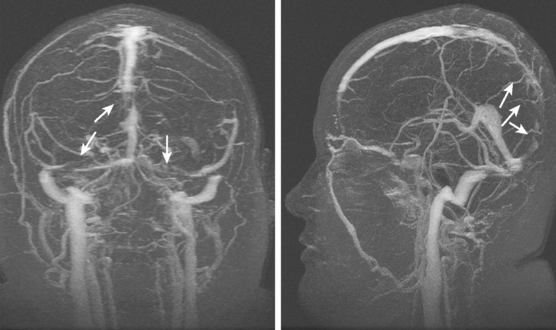

Для подтверждения венозного застоя применяются современные инструментальные методы исследования:

- Компьютерная томография (КТ) или магнитно-резонансная томография (МРТ) головного мозга. Эти методы позволяют с высокой точностью визуализировать изменения в тканях и сосудах главного органа центральной нервной системы.

- Ангиография – инструментальный метод, который позволяет визуализировать сосуды головного мозга. Процедура помогает выявить участки сужения или закупорки сосудов, а также определить места и уровень их расширения, наличие кровотечений, опухолей и другие проблемы, которые невозможно диагностировать другими способами.

В последние годы внимание ученых привлекает использование неинвазивных методов диагностики, таких как ультразвуковая допплерография и магнитно-резонансная томография (МРТ). Эти методы позволяют визуализировать венозные структуры и оценить скорость кровотока, что способствует более точной диагностике ЗВОГМ. Исследования показывают, что ранняя диагностика и своевременное вмешательство могут значительно улучшить прогноз для пациентов.